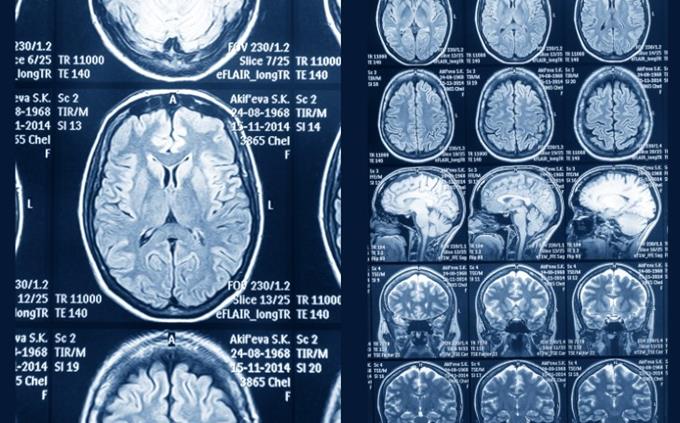

Functional MRI (fMRI) measures...

Blood oxygen level changes

Which modality is most sensitive for detecting acute brain hemorrhage?

CT

EEG wave patterns are categorized into bands such as...

Alpha, Beta, Delta, Theta